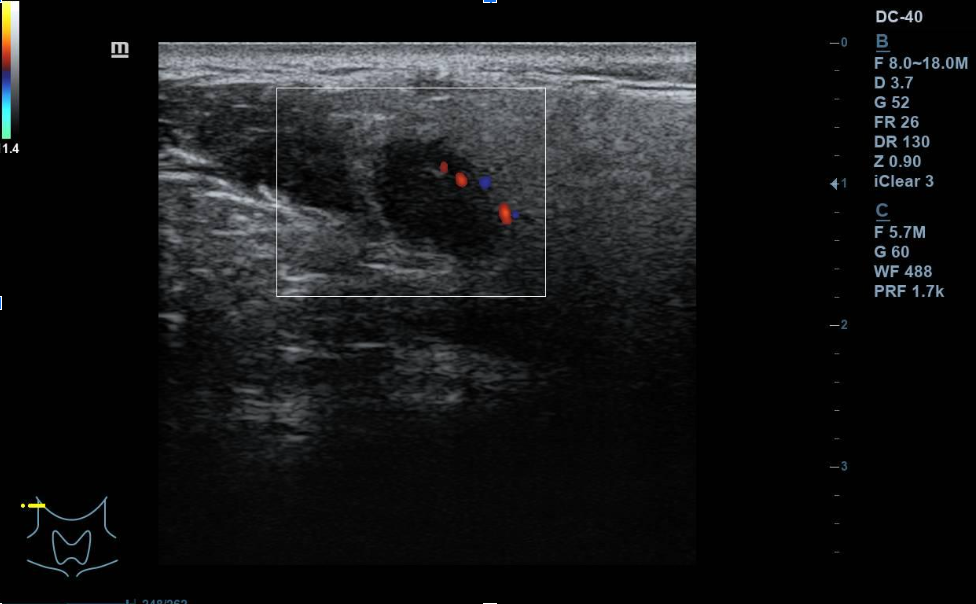

Se aprecian al menos dos lesiones intraparotídeas, una menor hipoecogénica, redondeada de unos 10 mm de diámetro máximo, doppler con vascularización mixta. La mayor de unos 3 cm de diámetro máximo, hipoecogénica, de contenido irregular, con áreas anecogénicas, de características sólidas, bien definido. Vascularización mixta, central y periférica. No se observan adenopatías cervicales de aspecto ecográfico patológico. La parótida contralateral, impresiona de normalidad.